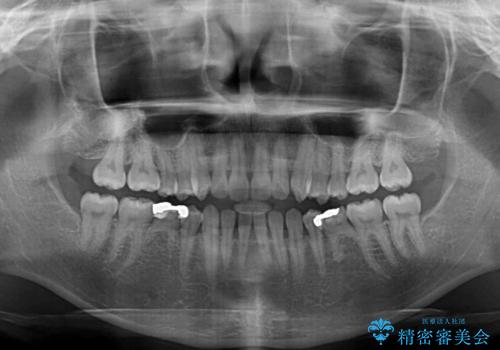

- 前歯の隙間を気にして来院された患者様です。

隙間や叢生の程度はそれほど著しいものではなかったので、インビザラインでもワイヤー矯正でも対応可能でしたが、極力目立たない装置を希望されたため、インビザラインにて矯正治療を行うこととしました。

すきっ歯の原因は色々ありますが、嚥下や発音時の舌突出癖が大きな原因となることがあります。

こちらの患者様も強い突出癖があったため、舌のトレーニング指導を行いました。